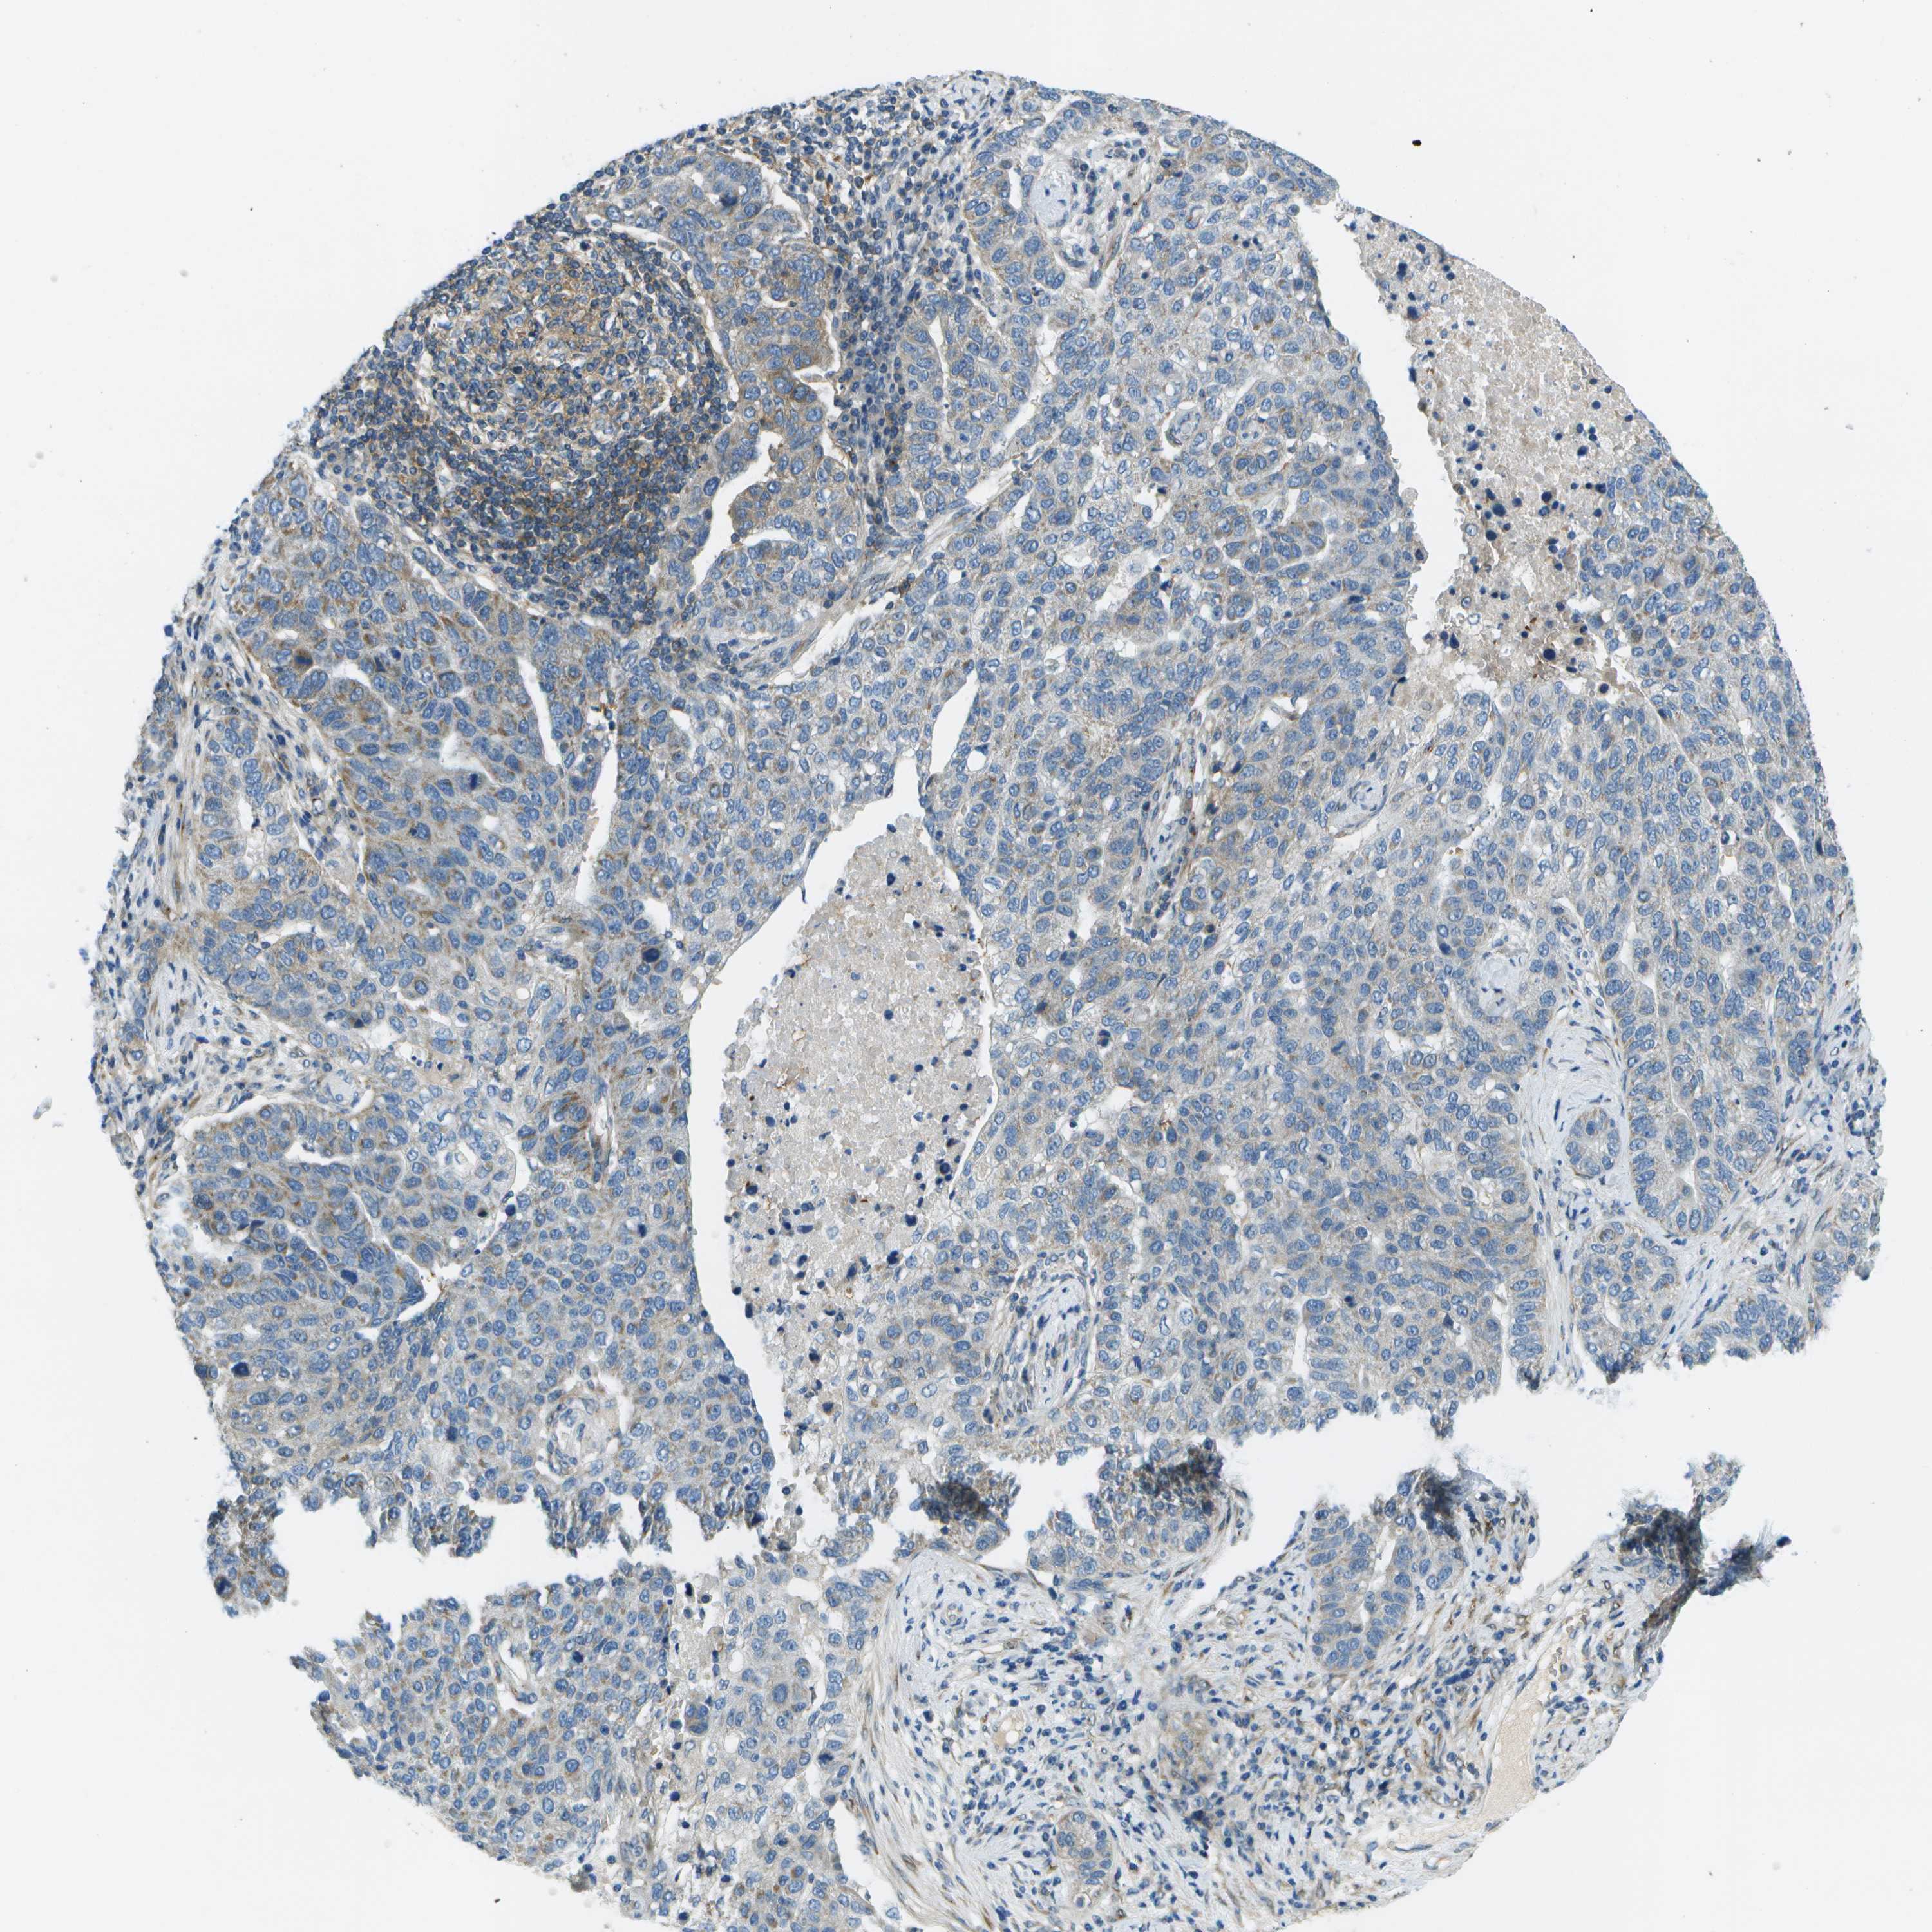

PANCREATIC CANCER - Protein expressioni

A mouse-over function shows sample information and annotation data. Click on an image to view it in a full screen mode. Samples can be filtered based on level of antibody staining by selecting one or several of the following categories: high, medium, low and not detected. The assay and annotation is described here.

Note that samples used for immunohistochemistry by the Human Protein Atlas do not correspond to samples in the TCGA dataset.

Antibody stainingi

Antibody staining in the annotated cell types in the current human tissue is reported as not detected, low, medium, or high, based on conventional immunohistochemistry profiling in selected tissues. This score is based on the combination of the staining intensity and fraction of stained cells.

Each image is clickable and will lead to virtual microscopy that enables deeper exploration of all samples and also displays staining intensity scores, fraction scores and subcellular localization as well as patient and tissue information for each sample.

Antibody HPA016865

Antibody HPA024801

Adenocarcinoma, NOS